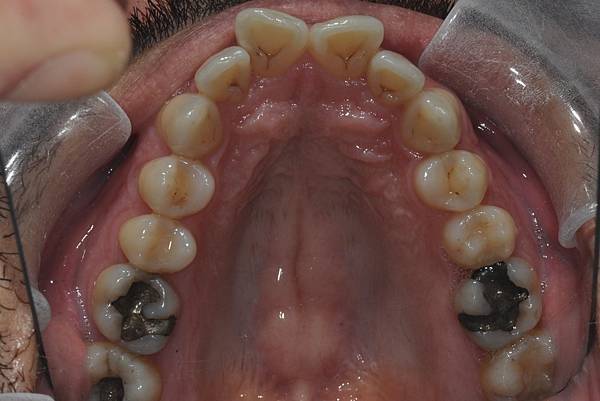

台灣的牙科醫療品質, 連外國人都說讚!此案例為深咬合併二級咬合 林醫師藉由正中上顎骨釘(HPPG technique)做上顎全齒列後移改善暴牙 讓本來五官就相當立體的艾先生,笑起來更燦爛了! 治療前/治療後-以上案例由林昇進醫師提供 分享到